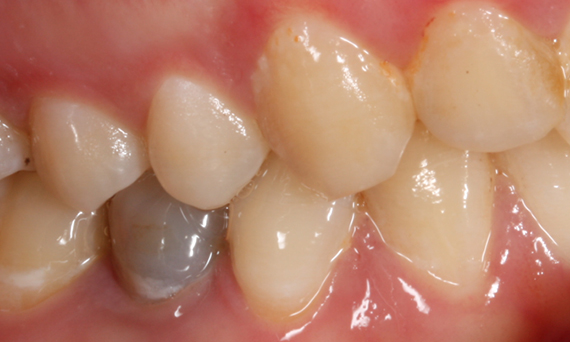

Before

Insufficient fillings in the second quadrant. The restorations were about 15 years old.

After

Chairside-fabricated crowns made from CEREC Tessera (teeth 26/27). Inlays for teeth 24 and 25 made of composite blocks.